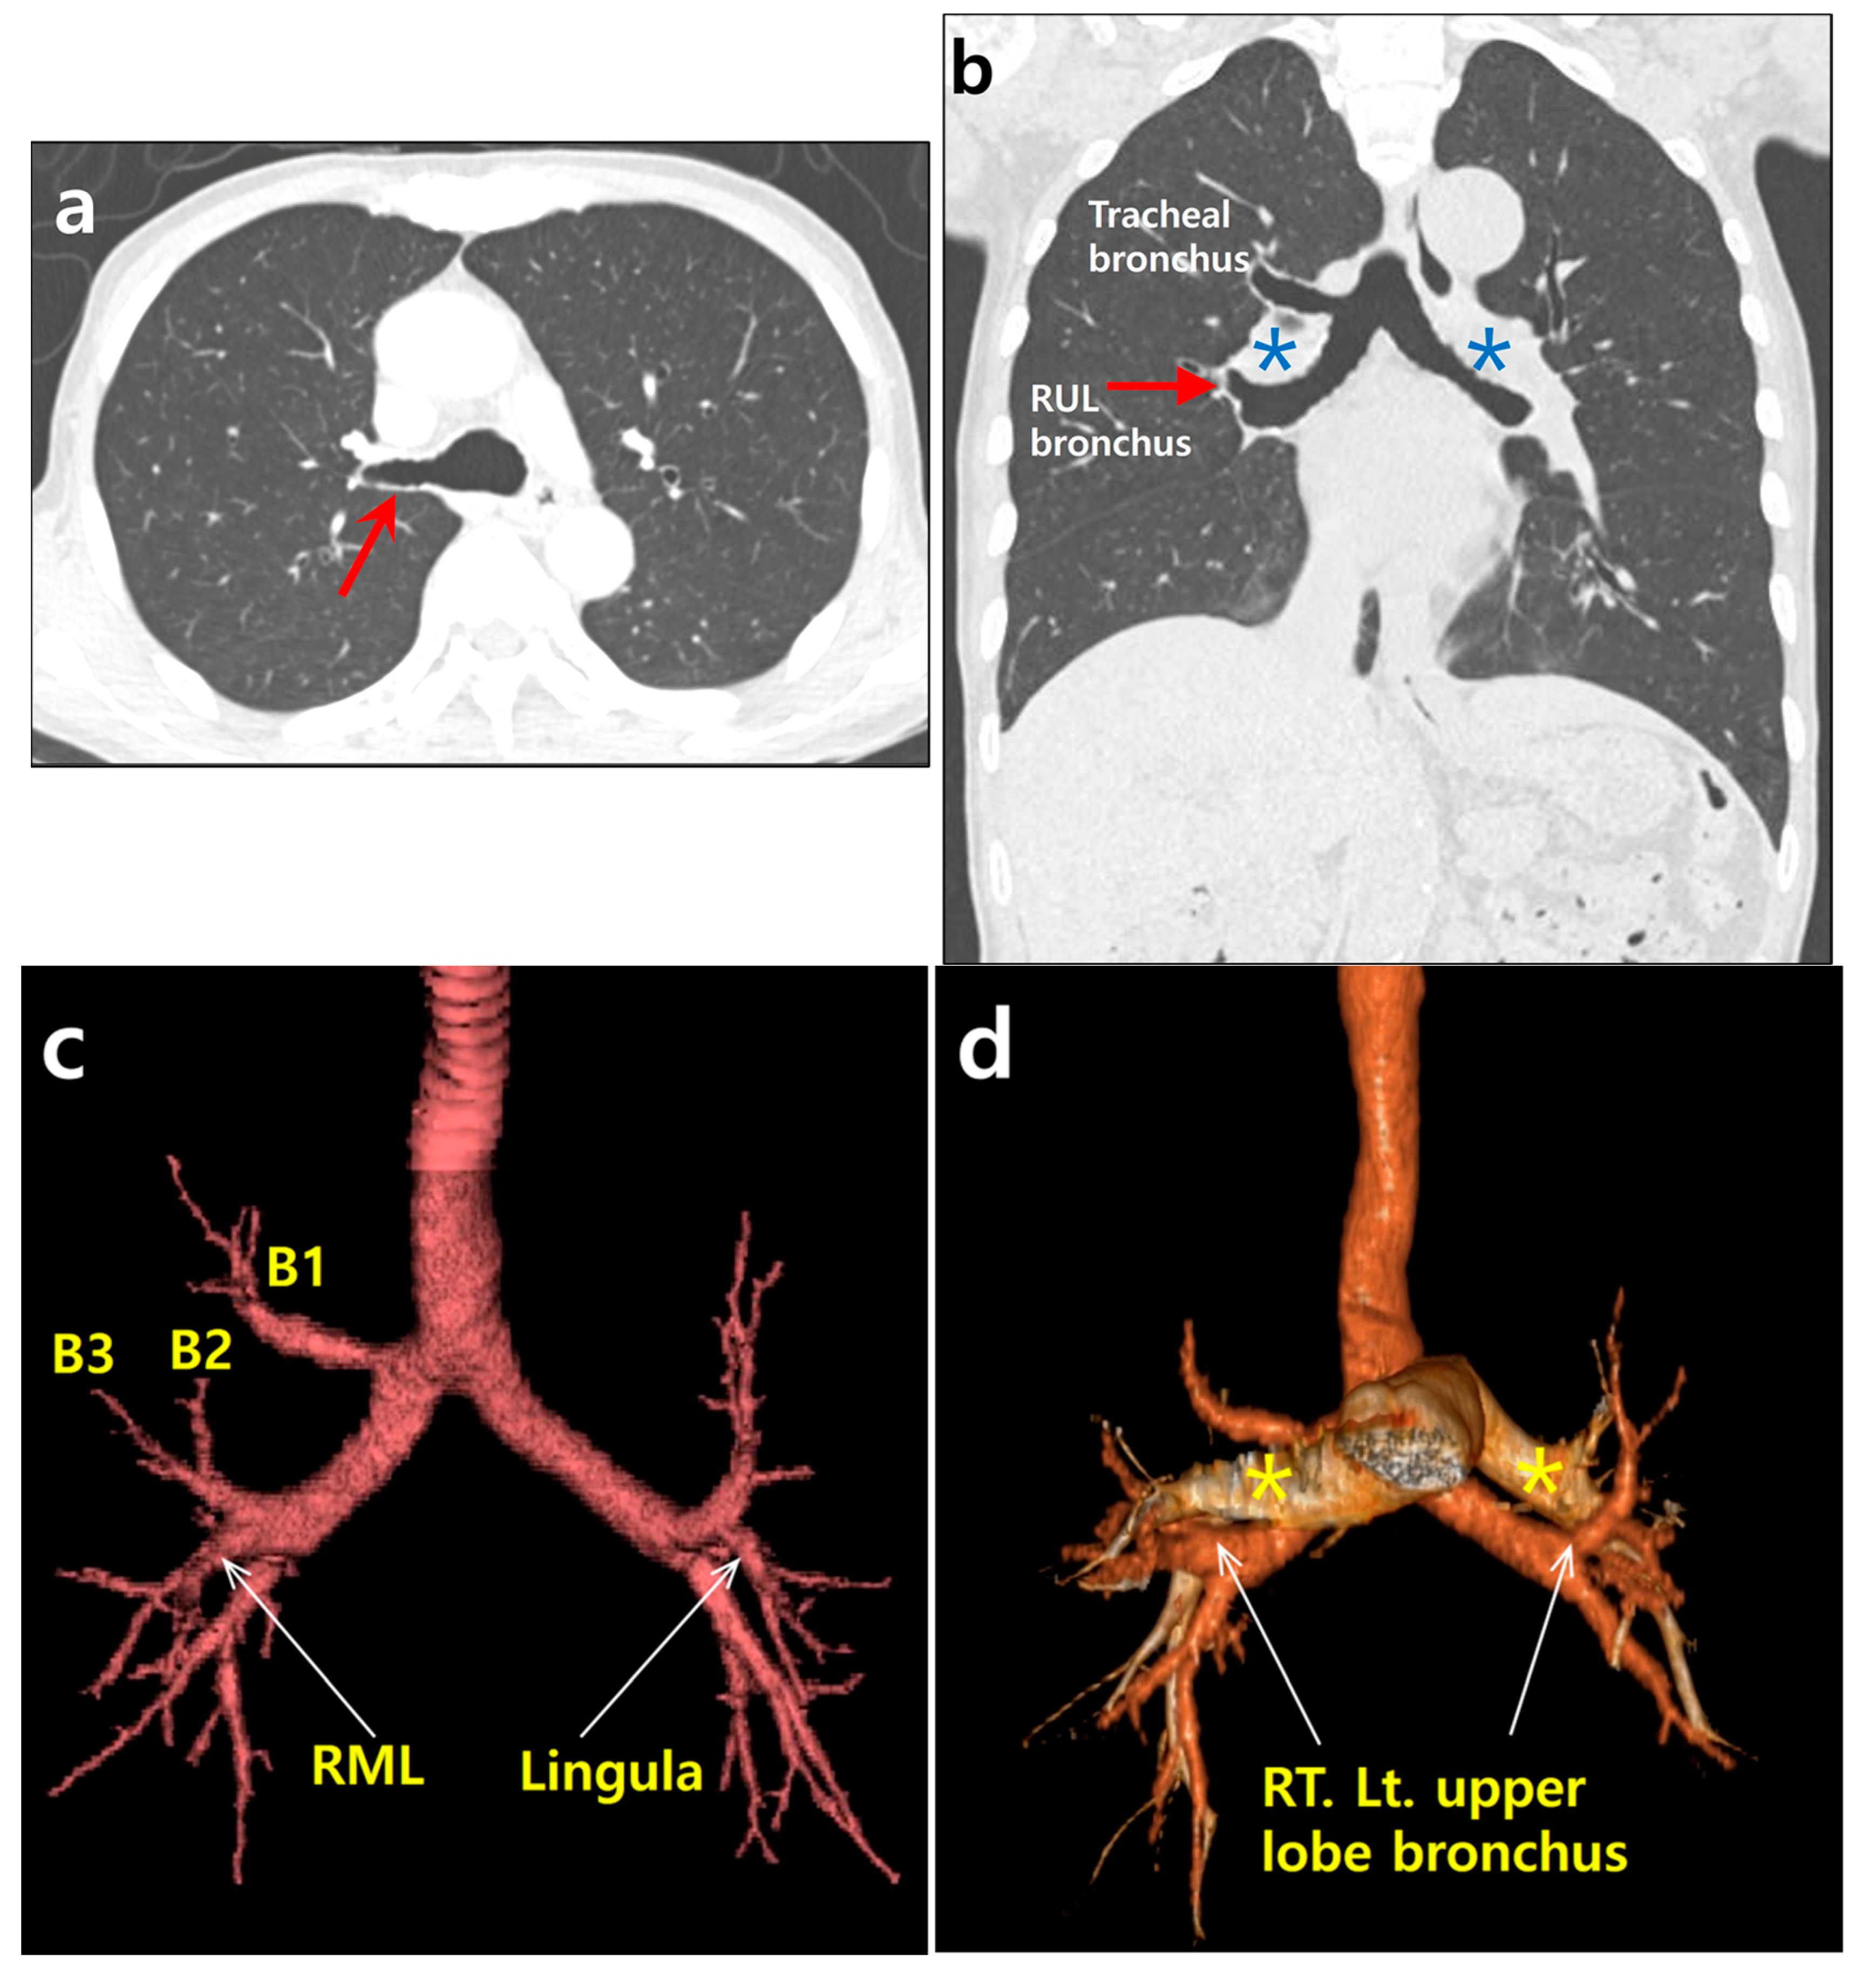

A 74 year old male patient was hospitalized with a progressive weakness of his arms that began seven months prior to hospitalization. Based on neurologic studies, he was diagnosed with amyotrophic lateral sclerosis. As he also complained of exertional dyspnea upon admission, an evaluation was performed for the presence of thoracic lesions. A chest X-ray showed unremarkable findings. A contrast-enhanced chest CT scan was also performed, showing no parenchymal infiltrates or pulmonary thromboembolism. However, there were tracheobronchial branching anomalies. At the level of the carina, an aberrant bronchus was noted, arising from the right main bronchus (tracheal bronchus) (Figure 1a). A coronal, reformatted image showed that both main bronchi were long, with right main bronchus resembling the left bronchus morphologically (Figure 1b). A reconstructed, 3D CT image of the tracheobronchial tree revealed a symmetrical bronchial branching pattern of both bronchi. Similar to the left upper lobe bronchus, the right middle lobe bronchus (B4 and B5) arose with the upper lobe bronchus (Figure 1c). A tracheal bronchus arising from the right main bronchus corresponded to a displaced apical segmental bronchus (B1) of the right upper lobe. A superimposed, three dimensional (3D) CT image of the tracheobronchial tree and pulmonary arteries showed that both upper lobe bronchi were hyparterial. The upper lobe bronchus arose below the point where the ipsilateral pulmonary artery crossed the main bronchus (Figure 1d). Both lungs were bilobed (Figure 1e). There was no minor fissure in the right lung. Further systemic evaluation did not reveal any congenital cardiovascular disease or abdominal visceral malposition. Therefore, the patient was diagnosed as having an isolated bronchial branching anomaly, left bronchial isomerism with a right-sided, eparterial tracheal bronchus. Despite bronchial anomaly, it was determined that the patient’s respiratory symptoms were attributed to progressive amyotrophic lateral sclerosis.

Figure 1.

A 74 year old man with tracheal bronchus and left bronchial isomerism. (a) An axial chest CT image with lung window setting showing an aberrant bronchus (tracheal bronchus, arrow) arising from the right main bronchus at the level of carina. (b) A coronal, reformatted chest CT image with lung window setting showing symmetrical long both main bronchi resembling the left bronchus morphologically. Right upper lobe bronchus (RUL) is located below the point where the pulmonary artery (asterisk) crosses the main bronchus as on the left (hyparterial). Note tracheal bronchus directing towards the right upper lobe. (c) Reconstructed, 3D CT image of the tracheobronchial tree revealing both upper lobe bronchi in the same position. Similar to lingular division (arrow) of the left upper lobe bronchus, the right middle lobe bronchus (RML, arrow) arises with the right upper lobe bronchus. Displaced apical segmental bronchus (B1, thin arrow) arises from tracheal bronchus. Posterior and anterior segmental bronchi (B2 and B3) arise from right upper lobe bronchus. (d) Superimposed 3D CT image of the tracheobronchial tree and pulmonary arteries (asterisks) showing that both upper lobe bronchi (arrows) are hyparterial. (e) Sagittal reformatted CT images with lung window setting showing bilobed left and right lungs (arrows indicate both major fissures). There is no minor fissure in the right lung.